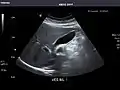

- Pancreas

Pancreas: Visualized portions unremarkable.